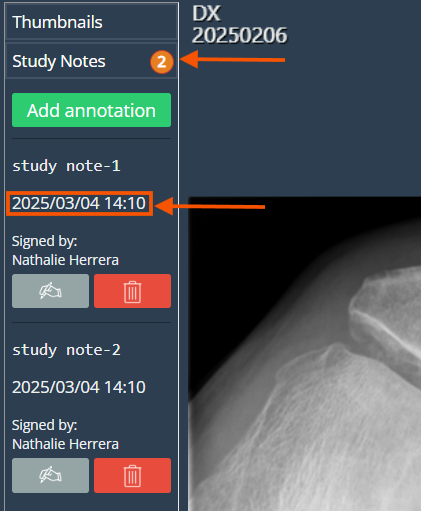

Study Notes

The "Study Annotations" feature has been renamed to "Study Notes" and remains located below the Thumbnails dropdown tab. This update introduces a timestamp displaying the date and time when a note is signed, along with a note counter in the tab for better tracking and organization.